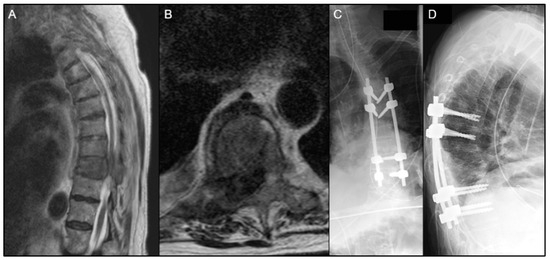

| Patient | Age/Sex | Primary Organ | Instrumented Levels | Radiation | Time to Wound Complication | Reoperation for Wound Complication |

|---|---|---|---|---|---|---|

| 1 | 58M | RCC | T10-L2 | Preop RT only | 48 days | No |

| 2 | 69M | Prostate ADK | T2-T9 | Preop RT only | 39 days | Yes |

| 3 | 44M | Lung ADK | T5-T9 | Postop EBRT | 14 days | Yes |

| 4 | 56F | Lung ADK | O-C5 | Postop EBRT | 22 days | Yes |

| 5 | 72M | Lung ADK | T1-T6 | Postop SBRT | 21 days | Yes |

| 6 | 52M | Lung ADK | C5-T5 | Postop EBRT | 22 days | Yes |

| 7 | 55M | Lung neuroendocrine | T5-T10 | No RT | 43 days | Yes |

| 8 | 67F | Unknown carcinoma | T11-S1 | No RT | 155 days | No |

| 9 | 74F | Lung neuroendocrine | T11-L3 | No RT | 22 days | Yes |

| 10 | 68F | Leiomyosarcoma | L3-S1 | No RT | 23 days | Yes |

| 11 | 75M | Adenocarcinoma | L1-L3 | No RT | 45 days | Yes |

| 12 | 65F | Thyroid | L4-S1 | No RT | 20 days | Yes |

| 13 | 68M | Lung ADK | L1-L3 | No RT | 84 days | Yes |

| 14 | 63M | Squamous-cell carcinoma/ENT | C7-T9 | No RT | 32 days | Yes |

| 15 | 65M | Melanoma | L1-L4 | No RT | 7 days | No |

| 16 | 56M | Squamous-cell carcinoma/ENT | T8-T10 | No RT | 8 days | Yes |

| 17 | 56F | RCC | T7-T11 | No RT | 46 days | Yes |